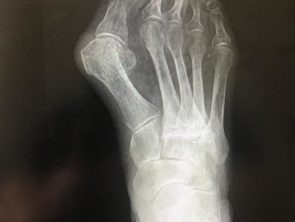

Примеры операций. #2 Hallux

Пациент – женщина 81 год.

Диагноз – вальгусная деформация первого пальца правой стопы третьей степени (Hallux Valgus)

Проведена операция: двухуровневая корригирующая остеотомия с фиксацией интрамедуллярной (внутрикостной) спицей

До операции